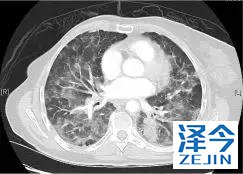

一位45岁的大姐诊断患有IV期NSCLC腺癌,肝脏和纵隔转移以及肥厚性骨关节病(HOA)症状,她曾接受过以前的铂类和培美曲塞治疗。

基因检测发现,NTRK融合基因,接受larotrectinib100 mg每日两次,出现快速反应,表现为第1周期(研究第8天)HOA症状,咳嗽和疲劳的改善以及第3周期完全没有咳嗽。第54天出现部分反应。反应持续时间> 12.88个月。